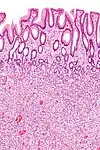

| Hyperplastic polyp of the stomach | Stomach | Elongated, tortuous, and cystic foveolae separated by edematous and inflamed stroma.[4] |  |